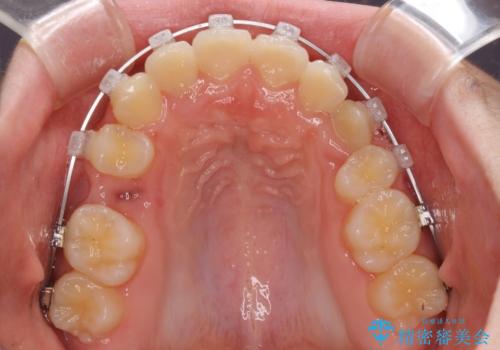

- クリアブラケット

- 2年1ヶ月

- 10-30回

下顎の乳歯は永久歯と比べて幅が大きいため、抜歯した場合のスペースが大きく、治療には長期間を要することが一般的です。

今回の患者様は中学生ということもあり、成人の患者様と比べ動きが速く、2年間で治療を終えることができました。